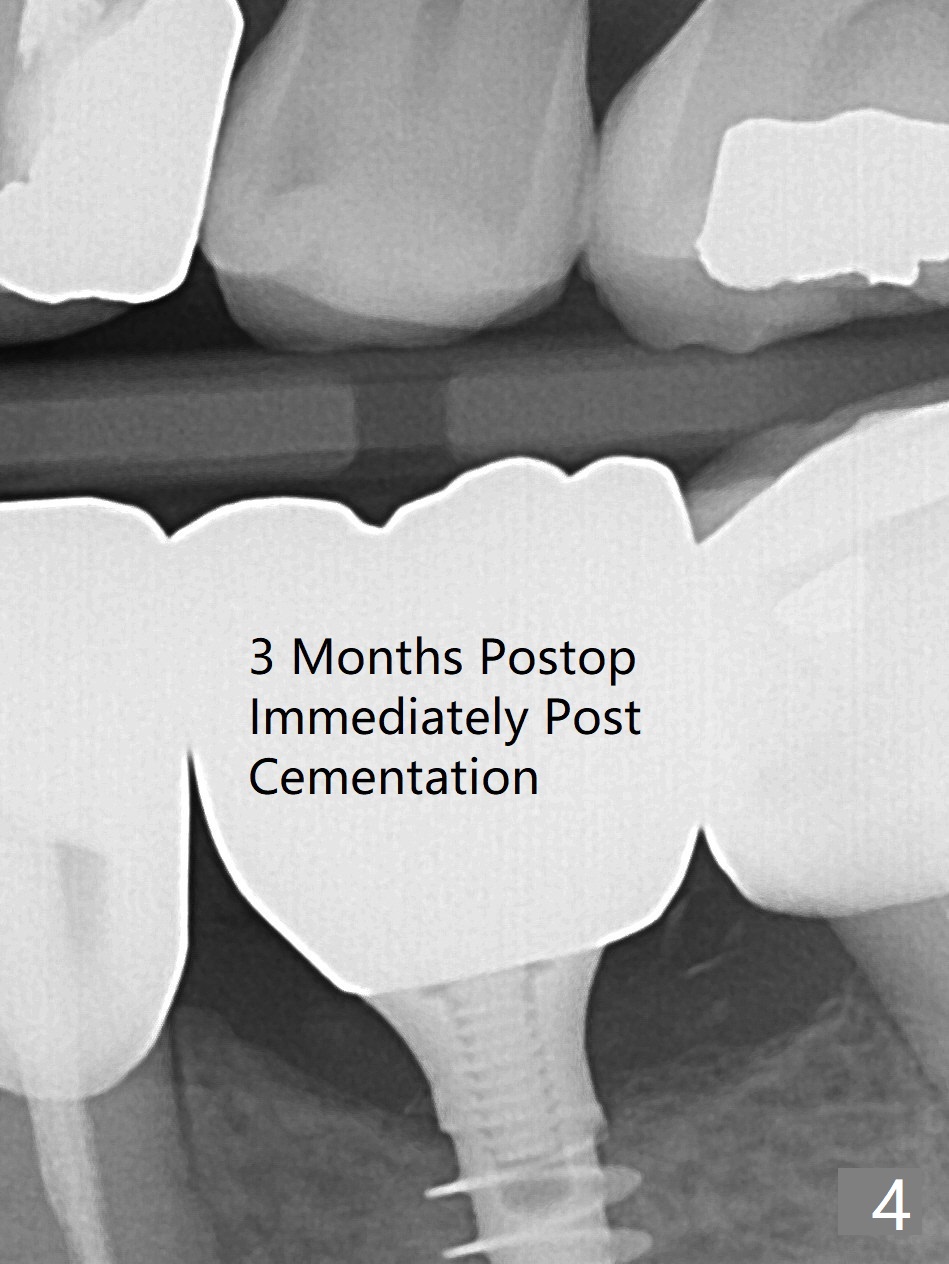

After finishing osteotomy at #19 according to IS drill sequence for 4x10 mm implant except cortical tap, a 4x9(2) mm Magicore is placed with ~ 50 Ncm (Fig.1). A 4.5x3 mm solid abutment is placed to check occlusion (Fig.2). There is discrepancy in osteotomy depth probably due to difference between the implant systems or overprep for subcrestal placement (narrow ridge, Fig.2 *). The implant could be 2 mm longer or the cuff could be longer (3 mm instead of 2 mm). The implant with 4.5x3 mm solid abutment is stable for impression nearly 3 months postop (Fig.3). Appreciate the distinct thread pattern of Magicore 3 months 1 week postop, immediately post cementation (Fig.4). Bone density increases 7 months post cementation (Fig.5 *). There is less likely implant fracture associated with a 1-piece one than a 2-piece one when a narrow one is placed in the narrow ridge.